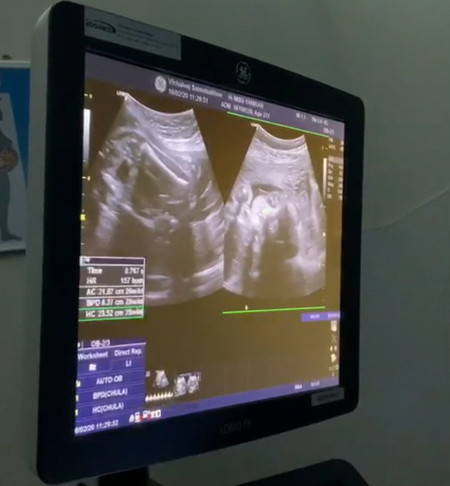

ตอนนี้ท้องได้ 27wแล้วค่ะ บ้านนี้ได้ลูกสาวค่ะ คุณแม่ท่านไหนกำหนดคลอดเดือน พค.บ้างค่ะ มาอวดรูปที่ไปซาวด์ เห็นหน้าน้องชัดๆให้ดูกันหน่อยค่ะ??